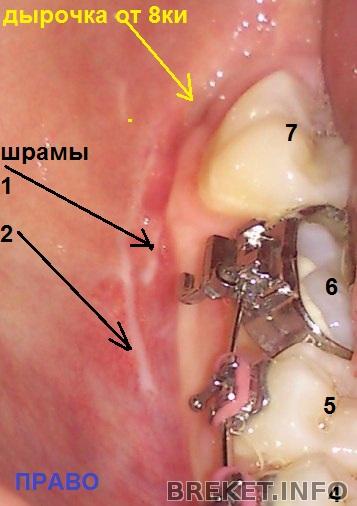

тем, кто помнит мою историю про , добавляю последствия) слева была удалена только 8ка, справа удалена восьмерка и дважды лазили искать ископаемые

слабонервным - форбидден!

А куда уехал центр?? Мда и шрамы "милые". Как же я рада, что мне не пришлось удалять мудрости